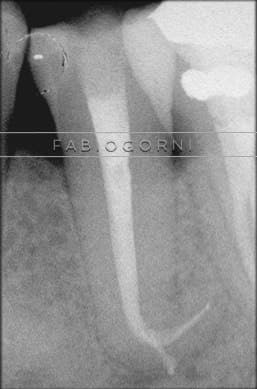

Загнутыми корень

Загнутыми корень 136 фотографий